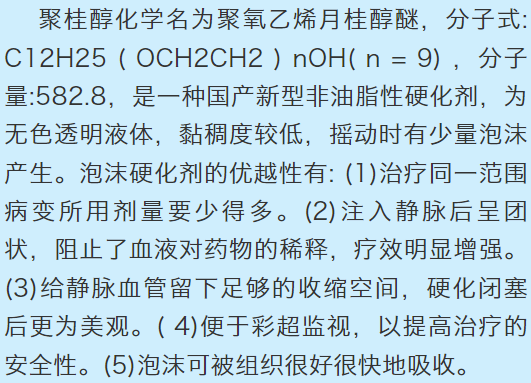

下肢静脉曲张X线造影图像!像蚯蚓一样在患者小腿之上萦绕!

下肢静脉曲张X线造影图像!像蚯蚓一样在患者小腿之上萦绕!